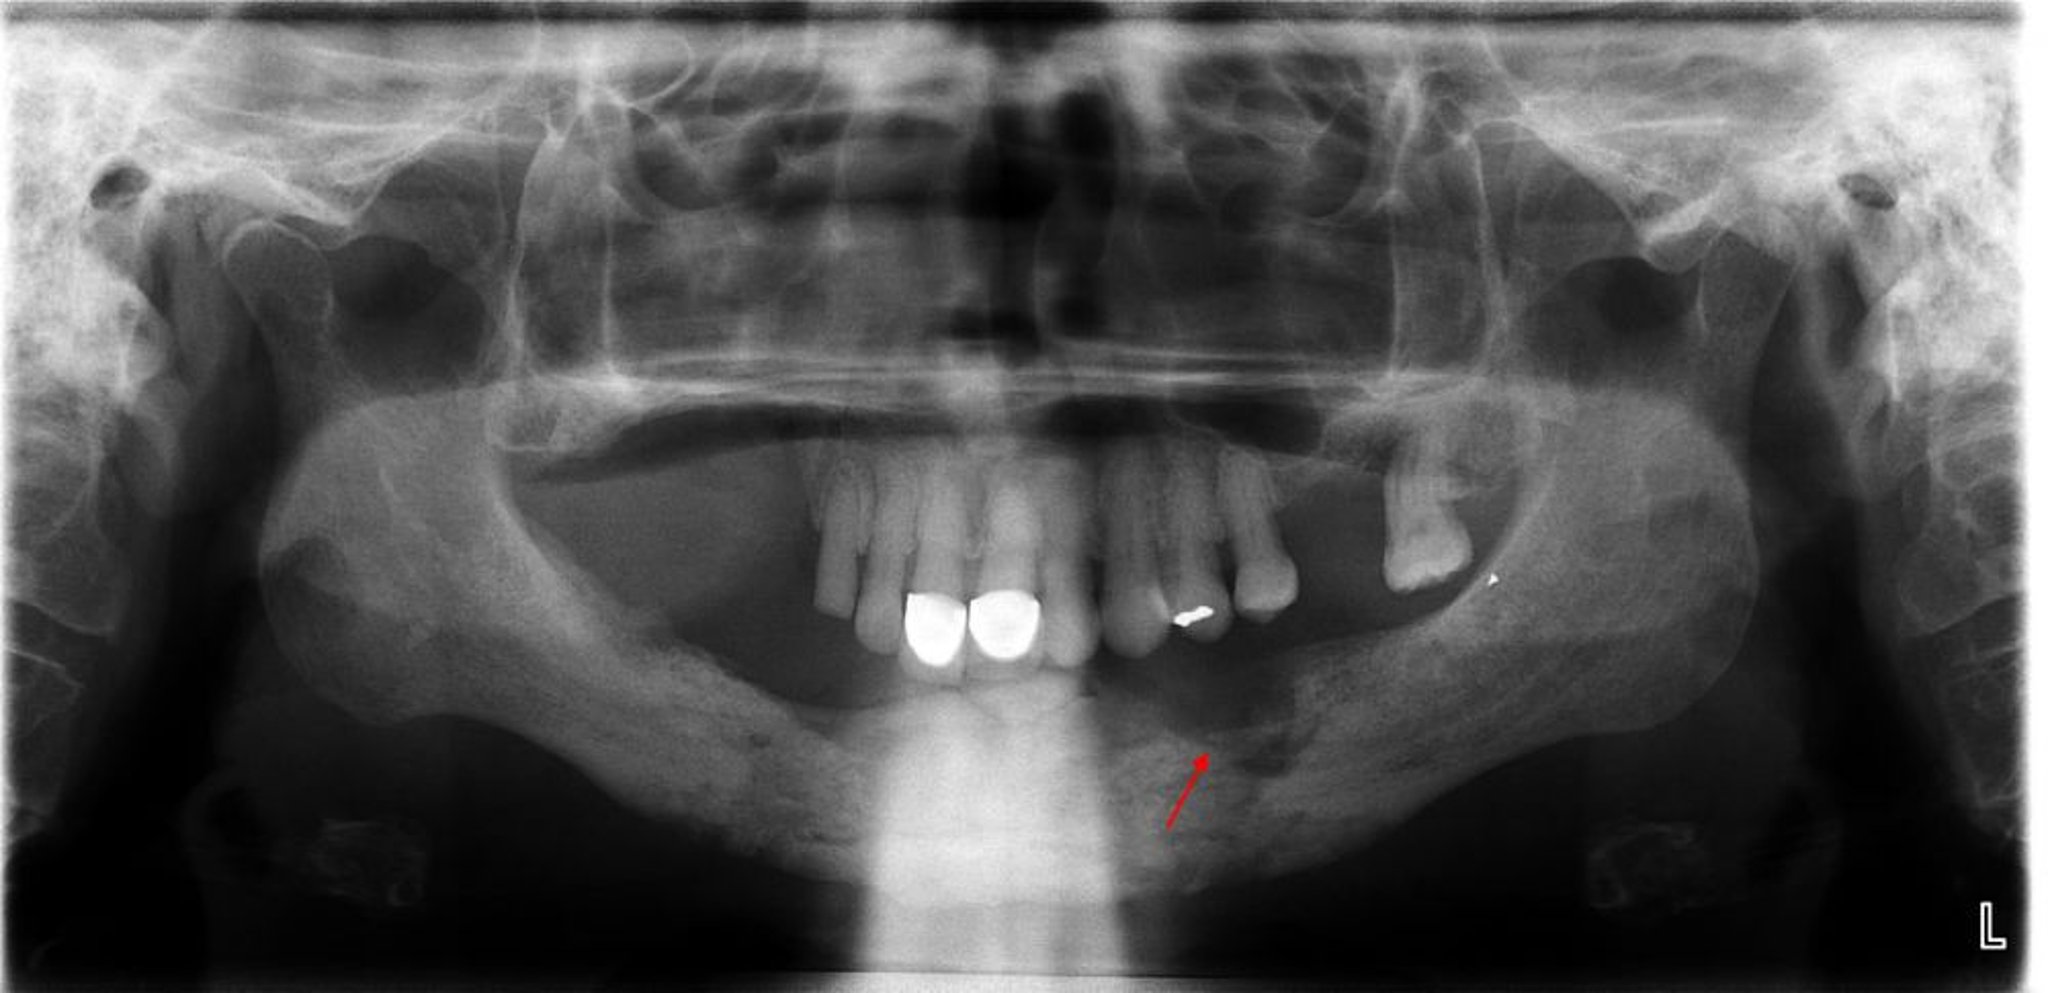

Questa RX rivela osteomielite con un evidente sequestro (osso non vitale) notato nel quadrante mandibolare sinistro (freccia).

Image courtesy of Byron (Pete) Benson, DDS, MS, Texas A&M University Baylor College of Dentistry.